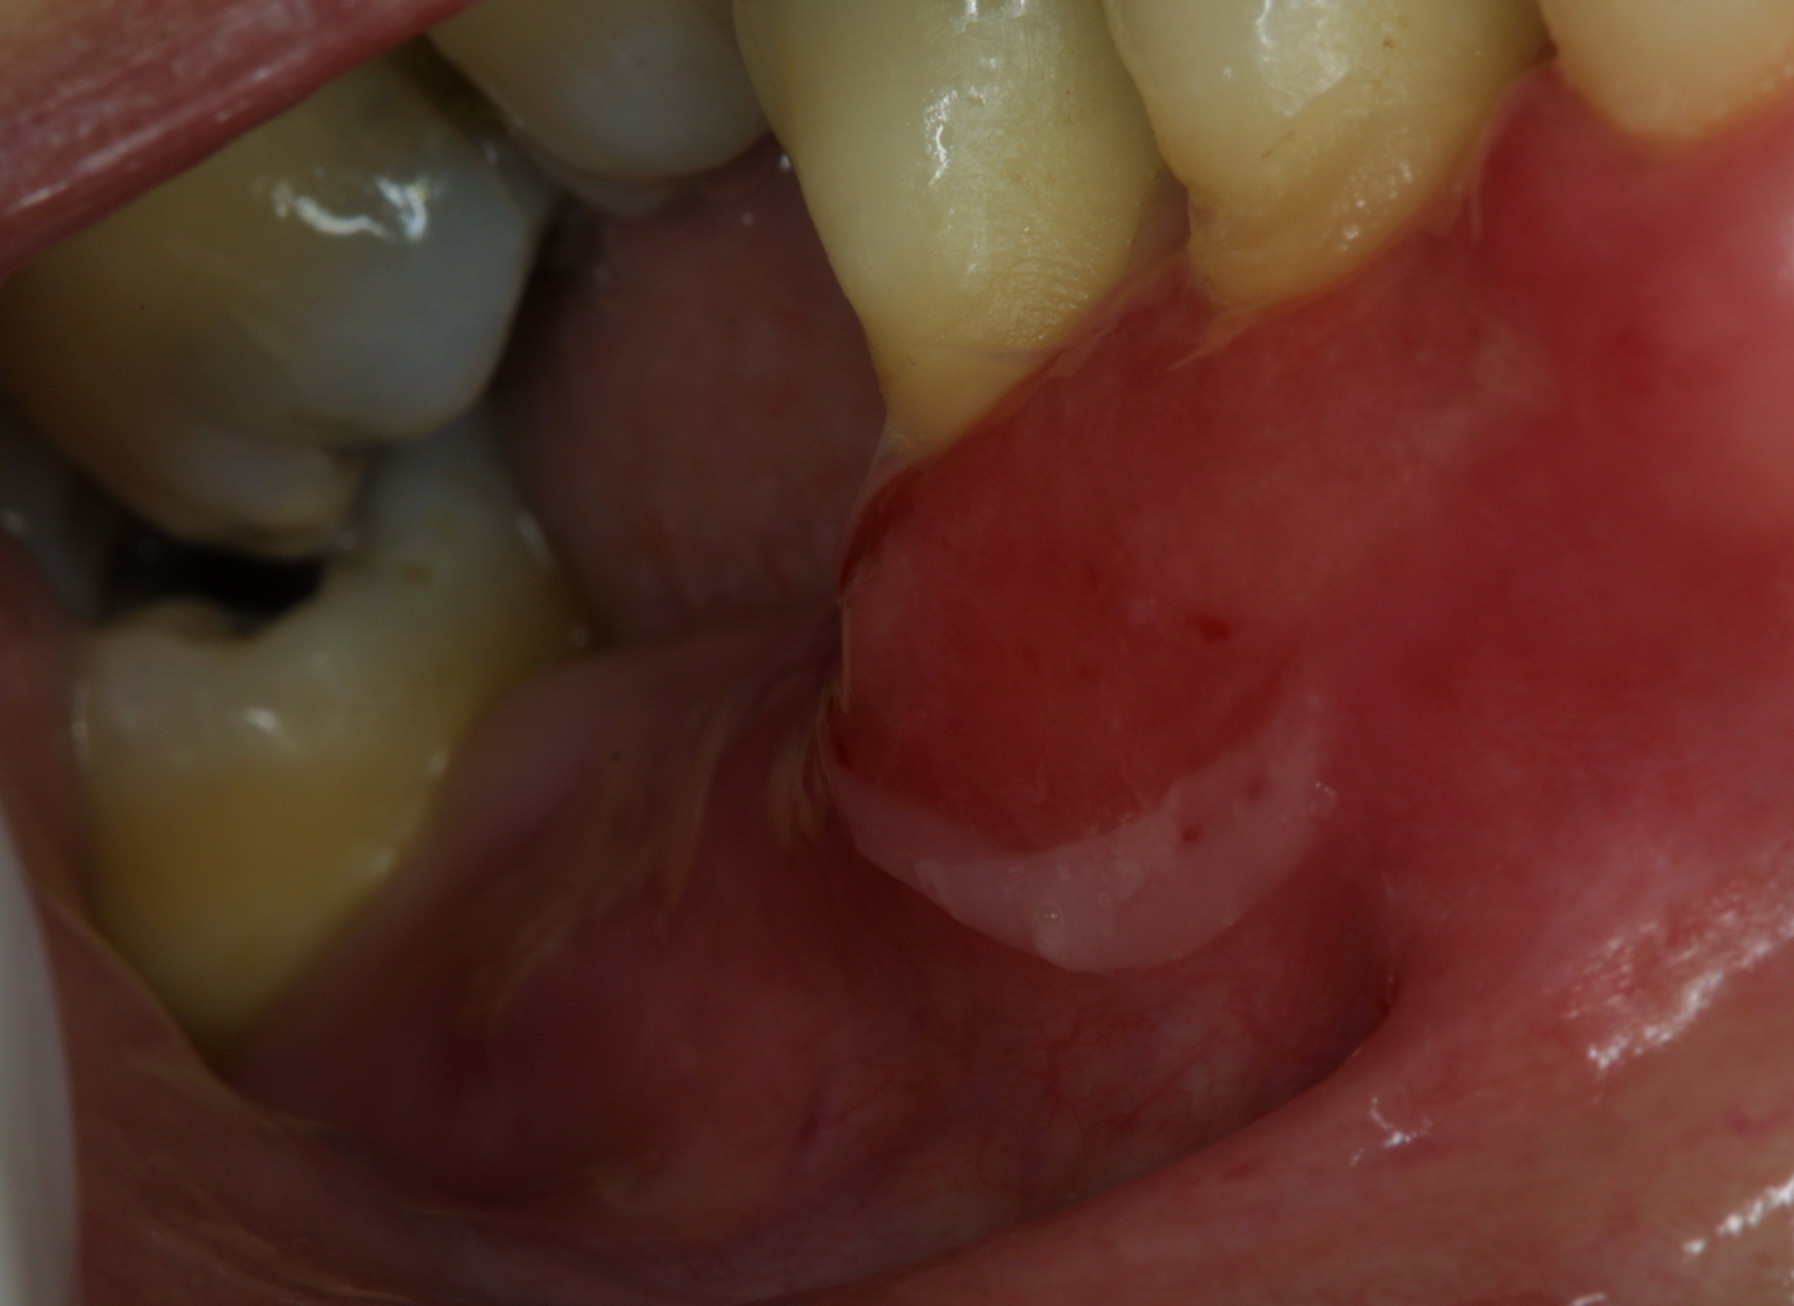

Mucosal and Cutaneous Lesions

The mouth is the most frequent site of involvement in patients with cicatricial pemphigoid; it is often the first (and only) site affected. Lesions often involve the gingiva, buccal mucosa, and palate ; other sites such as the alveolar ridge, tongue, and lips are also susceptible. A frequent oral manifestation is desquamative gingivitis. Other lesions may present as tense blisters that rupture easily or as mucosal erosions that form as a consequence of epithelial fragility. Lesions in the mouth may result in a delicate white pattern of reticulated scarring. In severe disease, adhesions may develop between the buccal mucosa and the alveolar process, around the uvula and tonsillar fossae, and between the tongue and the floor of the mouth. Gingival involvement can result in tissue loss and dental complications (e.g., caries, periodontal ligament damage, and loss of bone mass and teeth).